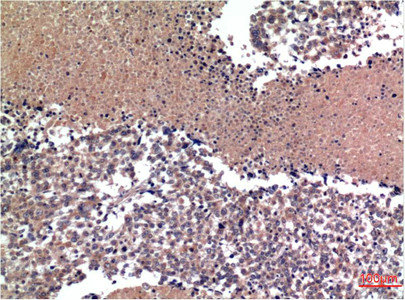

Immunohistochemical analysis of paraffin-embedded Human lung Tissue using Cyclin B1 Mouse mAb diluted at 1:200.

Immunohistochemical analysis of paraffin-embedded Human Tonsil Tissue using Cyclin B1 Mouse mAb diluted at 1:200.